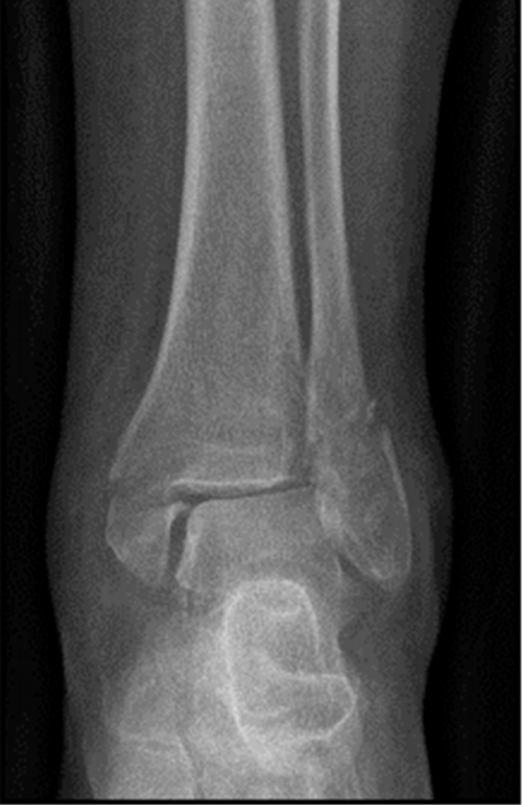

患者为83岁女性,于光滑平面滑倒后致三踝骨折,后踝为Bartonček 2型骨折,累及后外侧骨块及腓骨切迹(图2a–d)。相关合并症包括:骨量减少、软组织条件不良(皮肤呈羊皮纸样改变)、2型糖尿病(HbA1c 7.7%)。

image.png

(a)

(b)

(c)

(d)

图 2. (a–d):三踝骨折:(a) 前后位及 (b) 侧位X线片;(c) 轴位及 (d) 矢状位CT图像显示2型后踝骨折伴小中间骨块。